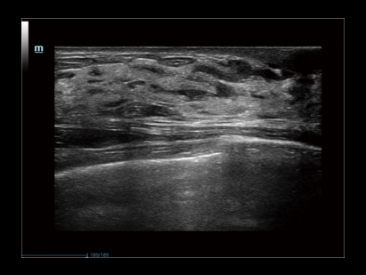

Функция используется для усиления и более четкого представления границ изображения в результате снижения шумов. Алгоритм подавления шума и артефактов от компании Mindray — iClear работает в 3D/4D режимах.